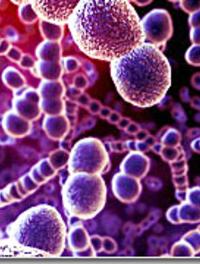

La fièvre de Lassa : plus que jamais d'actualité en 2018